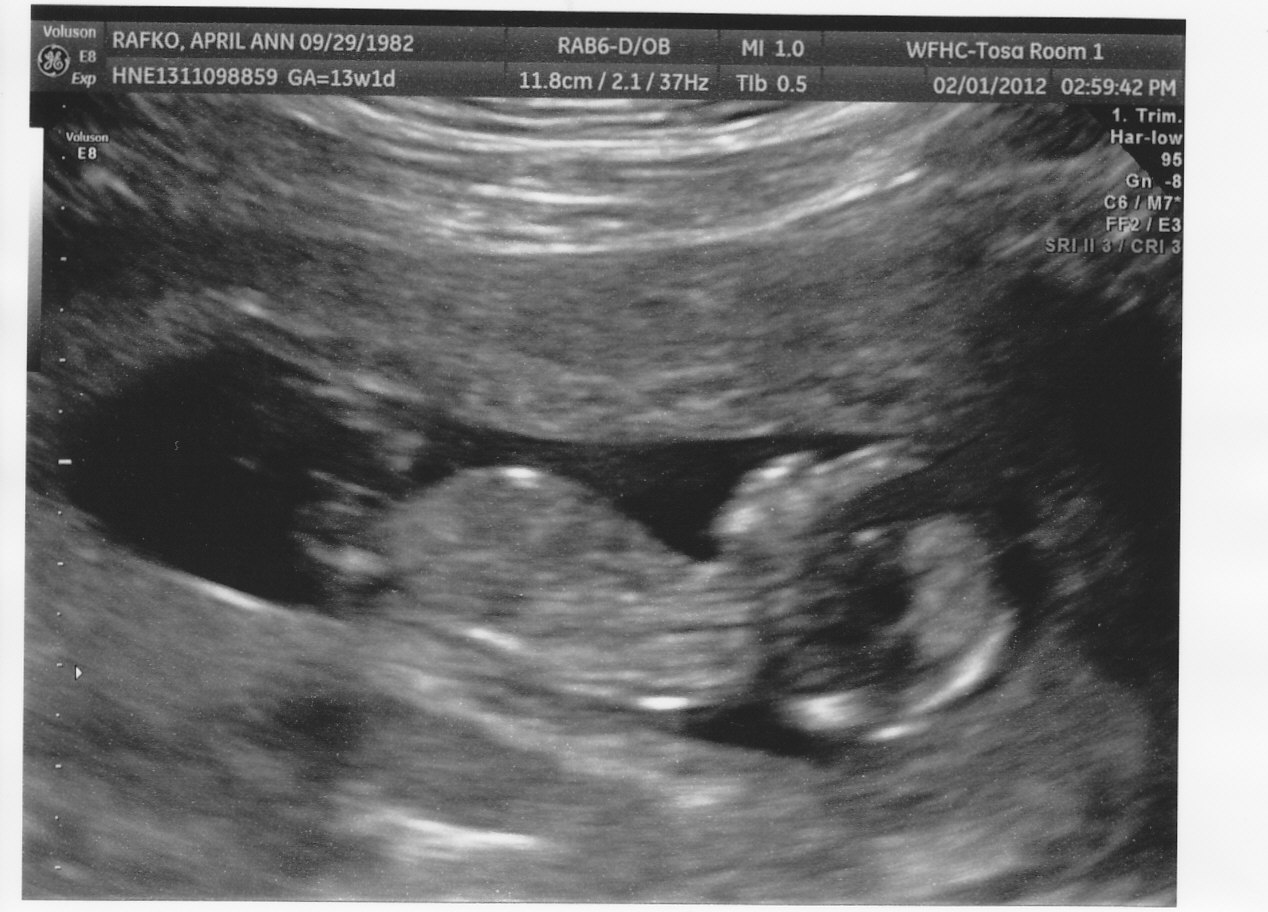

I'm not sure if it is visible or not. From what you can tell, do you think this baby is going to be a girl or a boy?

boy

I think boy too from the 1st pic, pitty the legs were closed in the second.

I'd guess boy from first pic as well.

I think boy too. :)

If you were 12 weeks I would be more comfortable saying boy, since the nub angle is slightly elevated... but I would expect it to be more elevated by 13 wks 3 day. I'll still say boy though.